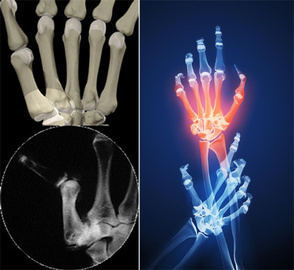

عضو هيأت علمي انستيتو پاستور ايران با بيان اين كه داروي اتانرسپت، دارويي جهت درمان بيماران مبتلا به آرتريت روماتوئيد است، اظهار كرد: اين بيماري جزء بيماريهاي التهابي مزمن و اتوايميون محسوب ميشود و علائمي چون التهاب مزمن مفاصل دستها و پاها همراه با التهاب در ارگانهاي غير مفصلي ديگر مانند پوست، قلب، ريه و چشم است كه در نهايت منجر به تخريب مفاصل، تغيير شكل مفصلي و افت فاحش در عملكرد مفاصل ميشود.